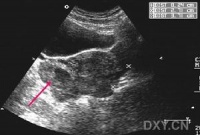

大多起病缓慢,迷走神经切断术者常于术后第2周开始进流质饮食后发病。主要症状有腹胀、上腹或脐周隐痛,恶心和持续性呕吐。呕吐物为混浊的棕绿色或咖啡色液体,呕吐后症状并不减轻。随着病情的加重,全身情况进行性恶化,严重者可出现脱水、碱中毒,并表现为烦躁不安呼吸急促、手足抽搐血压下降和休克。突出的体征为上腹膨胀,可见毫无蠕动的胃轮廓,局部有压痛叩诊过度回响,有振水声。脐右偏上出现局限性包块,外观隆起,触之光滑而有弹性、轻压痛,其右下边界较清,此为极度扩张的胃窦,称“巨胃窦症”,乃是急性胃扩张特有的重要体征,可作为临床诊断的有力佐证。

实验室检查可发现血液浓缩、低血钾、低血氯和碱中毒。立位腹部X线片可见左上腹巨大液平面和充满腹腔的特大胃影及左膈肌抬高.